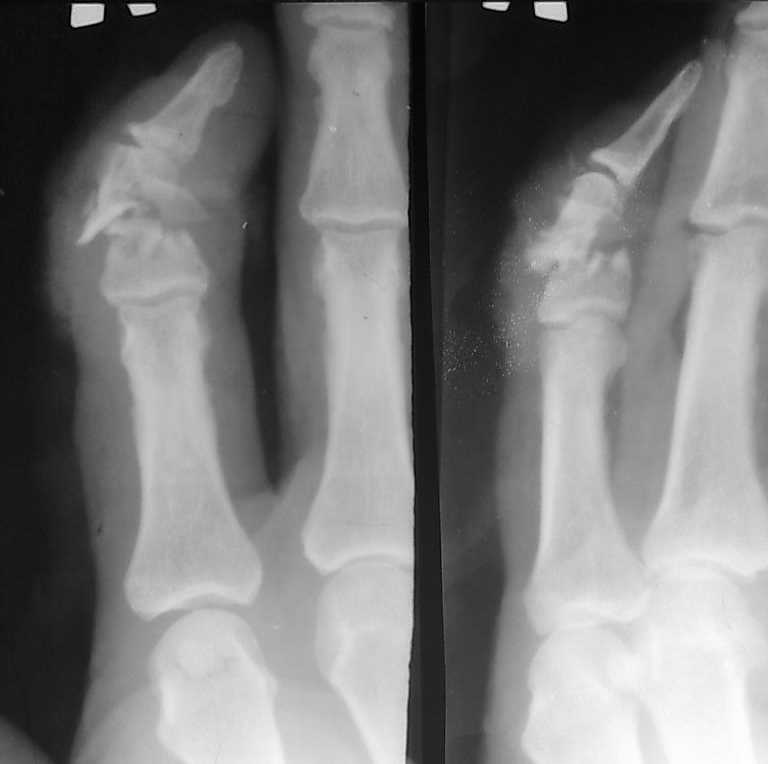

В связи с появлением и широкой популярностью шлифмашинок (в просторечии болгарки), травмы нанесенные этими прогрессивными агрегатами стали широко распространены. Характерной их особенностью являются переломы в виде линейных дефектов или ампутаций, чаще кистей-предплечий, стоп-голеней. Вот характерное наблюдение.

Очередной случай

Изображение